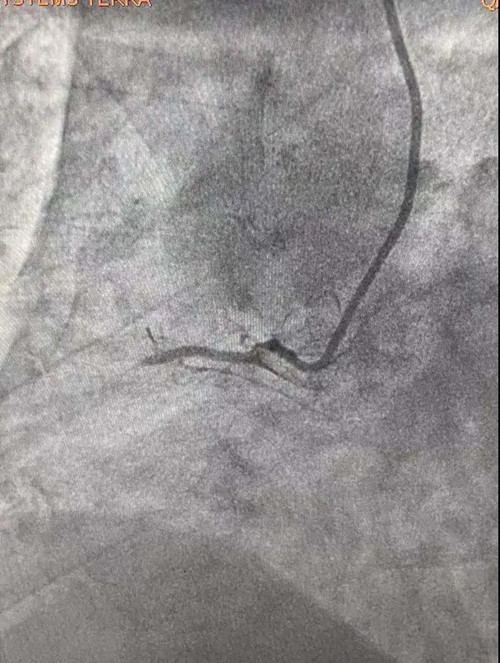

患者胸痛明显,伴有大汗,造影显示右冠近段严重百分之百闭塞,手术过程异常艰辛。重症医学科王秋艳介入团队医生应用1.5*15球囊反复小压力扩张,现在摆在医生面前的难题是既要打开血流又不能将血管扩撕,1.5球囊扩张后应用替罗非班,再次应用2.0球囊低压力持续扩张,此时显影出现右室支,患者症状立即缓解,血流恢复。由于患者右冠细小,不适合做支架,所以决定回病房继续药物治疗。